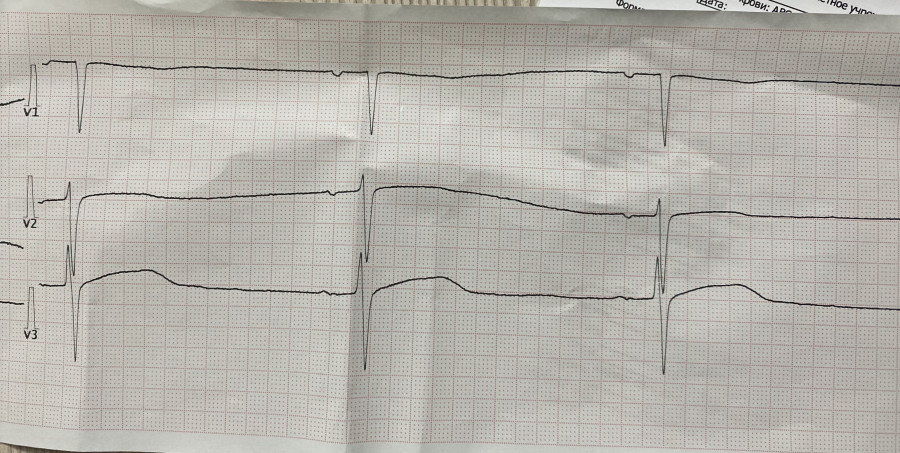

При ОИМ

Обсуждалось здесь https://vk.com/club84409679?w=wall-84409679_13004%2Fall